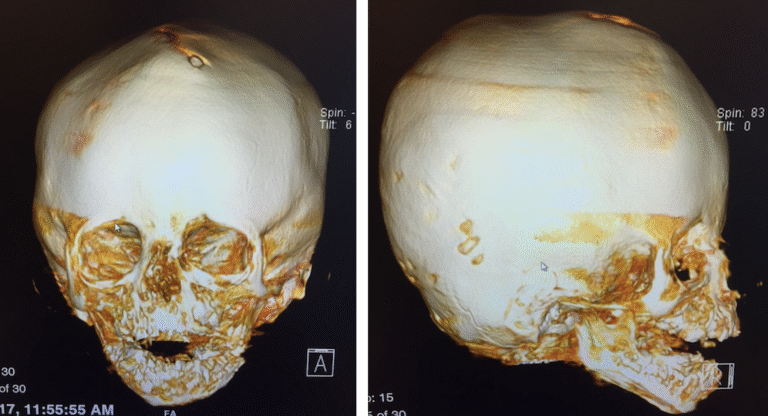

At El Paso Craniofacial Team, the primary treatment for craniosynostosis is surgery. First performed in the late 1800s, surgical approaches have continued to evolve and improve. The two main approaches are Calvarial Vault Remodel (CVR) and endoscopic-assisted surgery, with each tailored to the child’s age, the affected suture, and the severity of the condition.